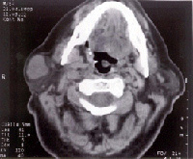

Adenoma Pleomorfo de Parótida, observamos claramente el parénquima parotídeo normal y el tumor mixto ( blanco) que abulta en el subcutáneo

El diagnostico clínico se completa con la punción aspiración que nos da el diagnostico y la tomografía axial computerizada que nos define su extensión y relaciones de vecindad. El tratamiento es quirúrgico y siempre precisa un abordaje tipo paratiroidectomía, identificando el nervio facial a su salida del agujero estilomastoideo, siguiéndolo hasta sus ramas terminales, si la lesión se limita al lóbulo superficial, se practica una parotidectomía suprafacial o de lóbulo superficial, pero si el tumor afecta al lóbulo profundo, precisaremos parotidectomía total, debiendo siempre respetar el nervio facial. La lesión que afecta a la glándula submaxilar se le debe escindir en su totalidad incluyendo el tumor preservando la rama mandibular del facial. La recidiva de estas lesiones suele ser debida a resección insuficiente, debiendo incluir en la segunda amplios márgenes de tejido, para prevenir recidivas adicionales, en estos pacientes puede ser inevitable sacrificar ramas del nervio facial, en determinados casos está indicada la sutura o el injerto nervioso.